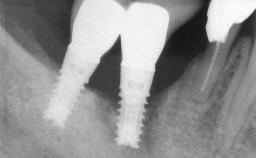

A 65-year-old female patient was referred to the periodontist for assessment and management of implant site 12. Implant 12 had been placed ten years previously and restored with a cemented single crown. The patient was a non-smoker in good general and periodontal health. On examination there were 7 mm probing depths at implant 12 with suppuration and bleeding on probing. The patient was aware of the presence of pus but had no discomfort. A periapical radiograph showed marginal bone loss to approximately the third thread of the implant. Previous radiographs obtained from the referring clinician indicated that there had been progressive bone loss since the implant was restored. A diagnosis of periimplantitis was made.